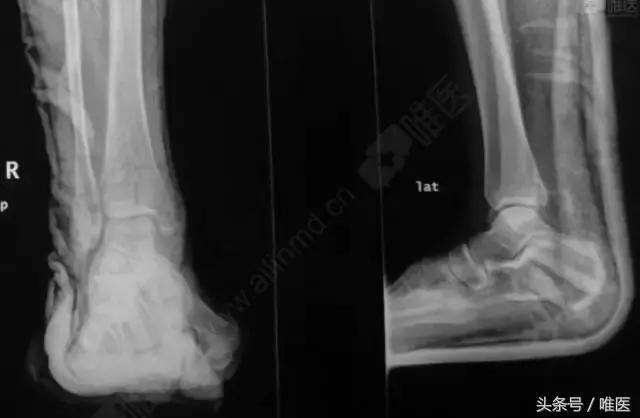

X线:右侧踝关节骨折

L-H分型:旋后外旋型 IV度;

Danis-Webber分型:B型

治疗前影像